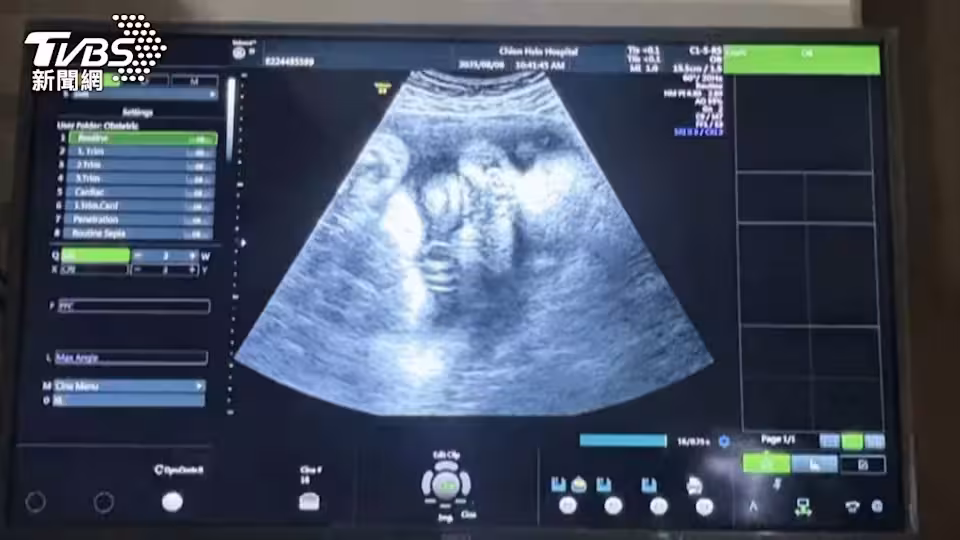

獨/產婦得A流高燒! 嬰誕生後腦麻亡 家屬控醫療疏失

對於這起事件,遭控醫院企劃組長許小姐回應:「媽媽的部分懷孕39周,待產體溫偏高,有給予退燒、克流感藥物,發生這樣情形深表遺憾。」婦產科醫學會秘書長則提醒:「孕婦要有警覺心,尤其高風險族群,周數越大越要小心。」

雖然雙方經衛生局調解未果,但醫界人士建議,A流盛行期間,孕婦若不慎感染可服用克流感藥物。孕婦發燒可能對胎兒造成影響,嚴重時會導致中樞神經損傷、早產等風險。專家呼籲孕婦除了避免感染病毒外,也要及早發現症狀並立即就醫治療。